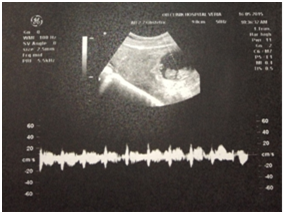

A 31 year old Gravida 3 Para 2 in her 10th+0 week of gestation was brought to our Ob/Gyn department by the ambulance because of acute onset lower abdominal pain followed by a syncopal episode. The patients’ pregnancy was confirmed by an obstetrical ultrasound performed 2 weeks prior to her presentation in our department and was described as a singleton intrauterine pregnancy. Her past obstetrical history included 2 uncomplicated caesarian sections 4 and 1 years earlier. On presentation the patient was hypotensive and tachycardic (BP: 90/60, HR: 102). The patient was resuscitated with IV fluids. On speculum examination a normal vagina and a closed cervix were noted. On bimanual examination the size of the uterus was consistent with a 10 week pregnancy. There was diffuse tenderness on palpation of the abdomen with decreased bowel sounds and Kehr sign positivity. (Acute pain in the tip of the shoulder due to the presence of blood or other irritants in the peritoneal cavity when a person is lying). Her hematocrit and hemoglobin were 23.2% and 7.5g/dL respectively. On transabdominal ultrasound a round gestational sac with a live fetus (CRL 10w+1) were revealed (Figure 1 & Figure 2). The sac was located in the lower anterior uterine segment. Free fluid was noted in the cul-de-sac.

Figure 2 FHR.